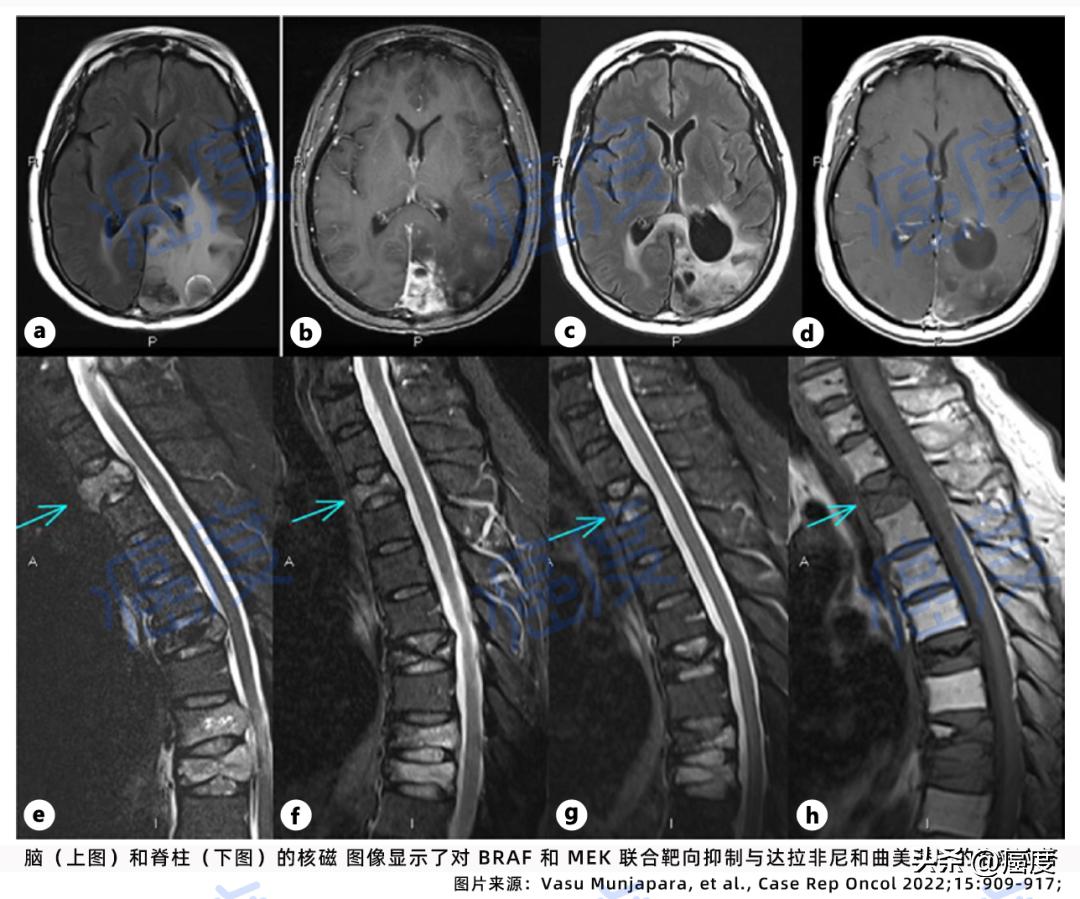

图.达拉非尼联合曲美替尼显示的治疗潜力

如上图所示,第一次治疗间隔扫描检查显示脑部、脊柱的肿瘤体积减少,右肺的病灶已经不存在了。患者对这个药物组合很耐受,没有出现不良症状。在整体治疗9个月后,患者的脑部病灶保持稳定。后面因出现了新的转移瘤无法有效的控制,患者转为临终关怀治疗。